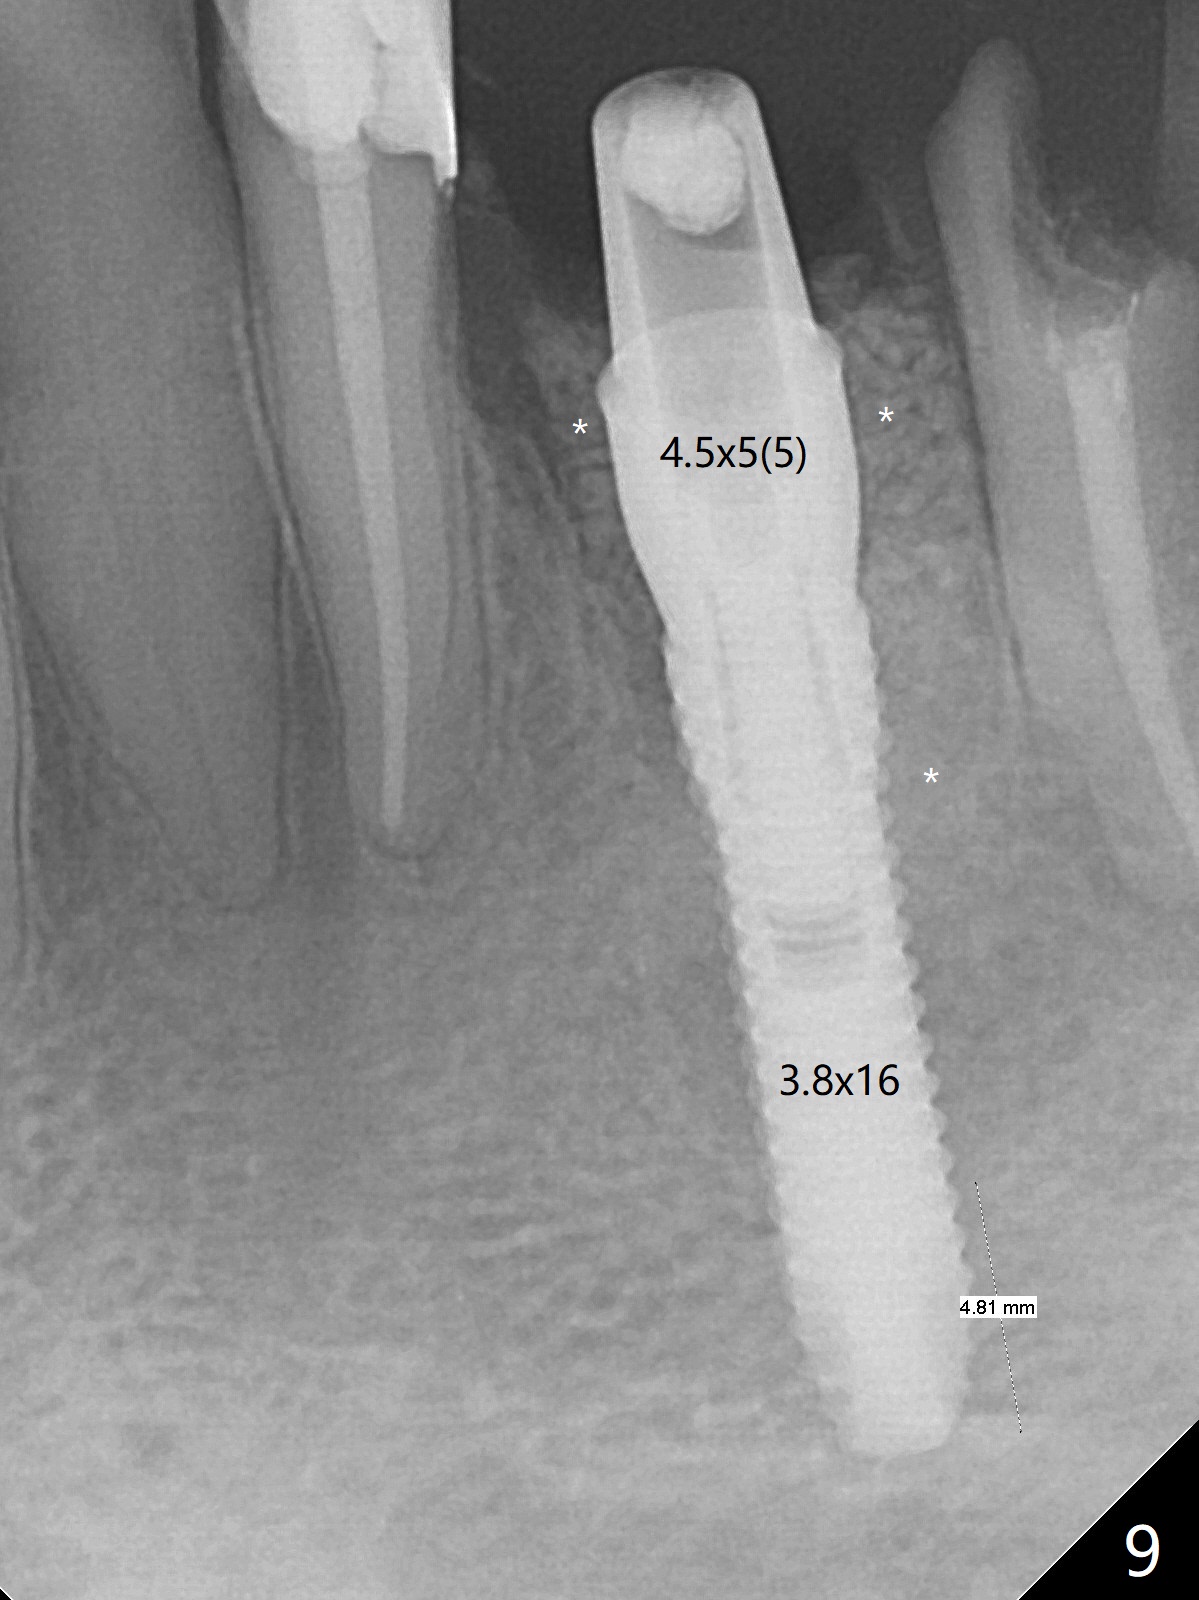

After removal of the split residual roots at #22 (Fig.1), the buccal wall is found to be defective, while the coronal portion of the lingual one (Fig.2 L) is confirmed to be more buccal than the apical portion. A vertical slot is made in the coronal portion of the lingual plate (Fig.3 *) in order to establish osteotomy lingual (Fig.4 O). The depth of the osteotomy in the apical native bone is 4.8 mm (Fig.5 CT coronal section). After the final drill (3 mm) is removed, a 3.8x16 mm implant is placed lingually for secure 2-pointed fixation (Fig.6,7, coronally: mesiolinguodistal; apically: in the native bone (Fig.9)). The essence of the lingual placement is the presence of a large buccal gap for Osteogen plug (Fig.8 yellow) and allograft (Fig.8 red, 9,10 (*)) for potential regeneration of the buccal plate. With bone graft and the overlying provisional (Fig.11 P), the buccal plate seems to have been established (*) 1 week postop. There is no obvious implant thread exposure 8 months postop (Fig.12). But the buccal plate is atrophic when the crown is cemented (~10 months postop, Fig.13).